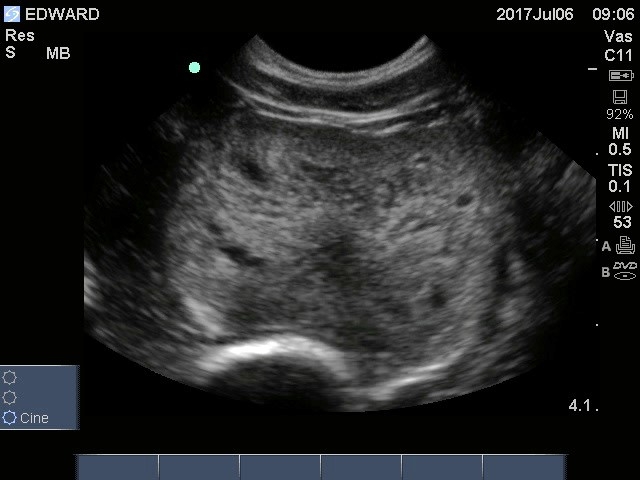

An ultrasound of a dog with prostatic disease